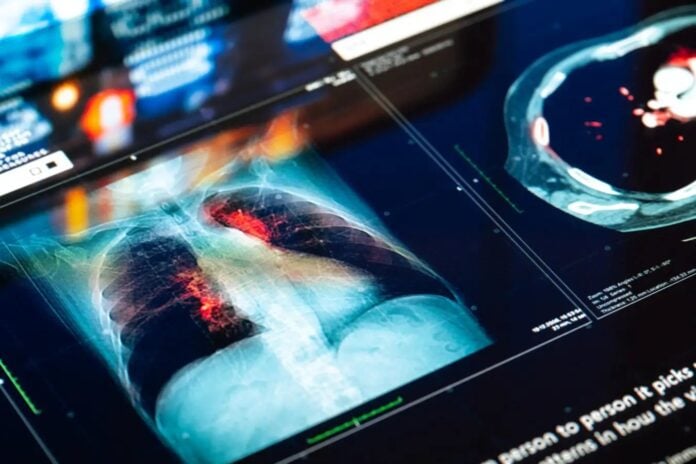

Втрата Y-хромосоми в клітинах раку легенів створює парадокс: це одночасно допомагає пухлинам уникнути імунної системи і робить певні ліки від раку більш ефективними. Це дивовижне відкриття підкреслює зростаюче розуміння того, як генетичні мутації в пухлинах можуть радикально змінити результати лікування.

Десятиліттями вчені знали, що чоловіки з віком втрачають Y-хромосому в деяких клітинах. Це явище, пов’язане з підвищеним ризиком серцево-судинних захворювань і скороченням очікуваної тривалості життя, зараз визнано критичним фактором прогресування раку. Дослідники на чолі з Донною ДеМео з Brigham and Women’s Hospital виявили, що в клітинах аденокарциноми легенів — найпоширенішого типу раку легенів — часто відсутні Y-хромосоми, на відміну від здорових клітин. Ця втрата відбувається незалежно від історії паління, що свідчить про те, що це не просто результат шкоди навколишньому середовищу.

Ключовим є не те, чи відбувається втрата, а скільки вона виражена в пухлині. Клітини з більшою втратою Y-хромосом демонструють знижену експресію антигенів, які зазвичай передають сигнал імунній системі. По суті, ракові клітини стають «невидимими» для Т-клітин, що дозволяє їм неконтрольовано рости. Це пояснює, чому пухлини без Y-хромосоми менш схильні до атаки природного захисту організму.

Хоча втрата Y-хромосоми допомагає в ухиленні від імунітету, вона парадоксально покращує реакцію на пембролізумаб, інгібітор імунної контрольної точки. Цей препарат працює, скасовуючи пригнічення Т-клітин, дозволяючи їм ефективніше атакувати ракові клітини. Дослідники проаналізували дані понад 800 пацієнтів з раком легенів і виявили, що пембролізумаб працював краще у тих, чиї пухлини мали втрату Y-хромосоми.